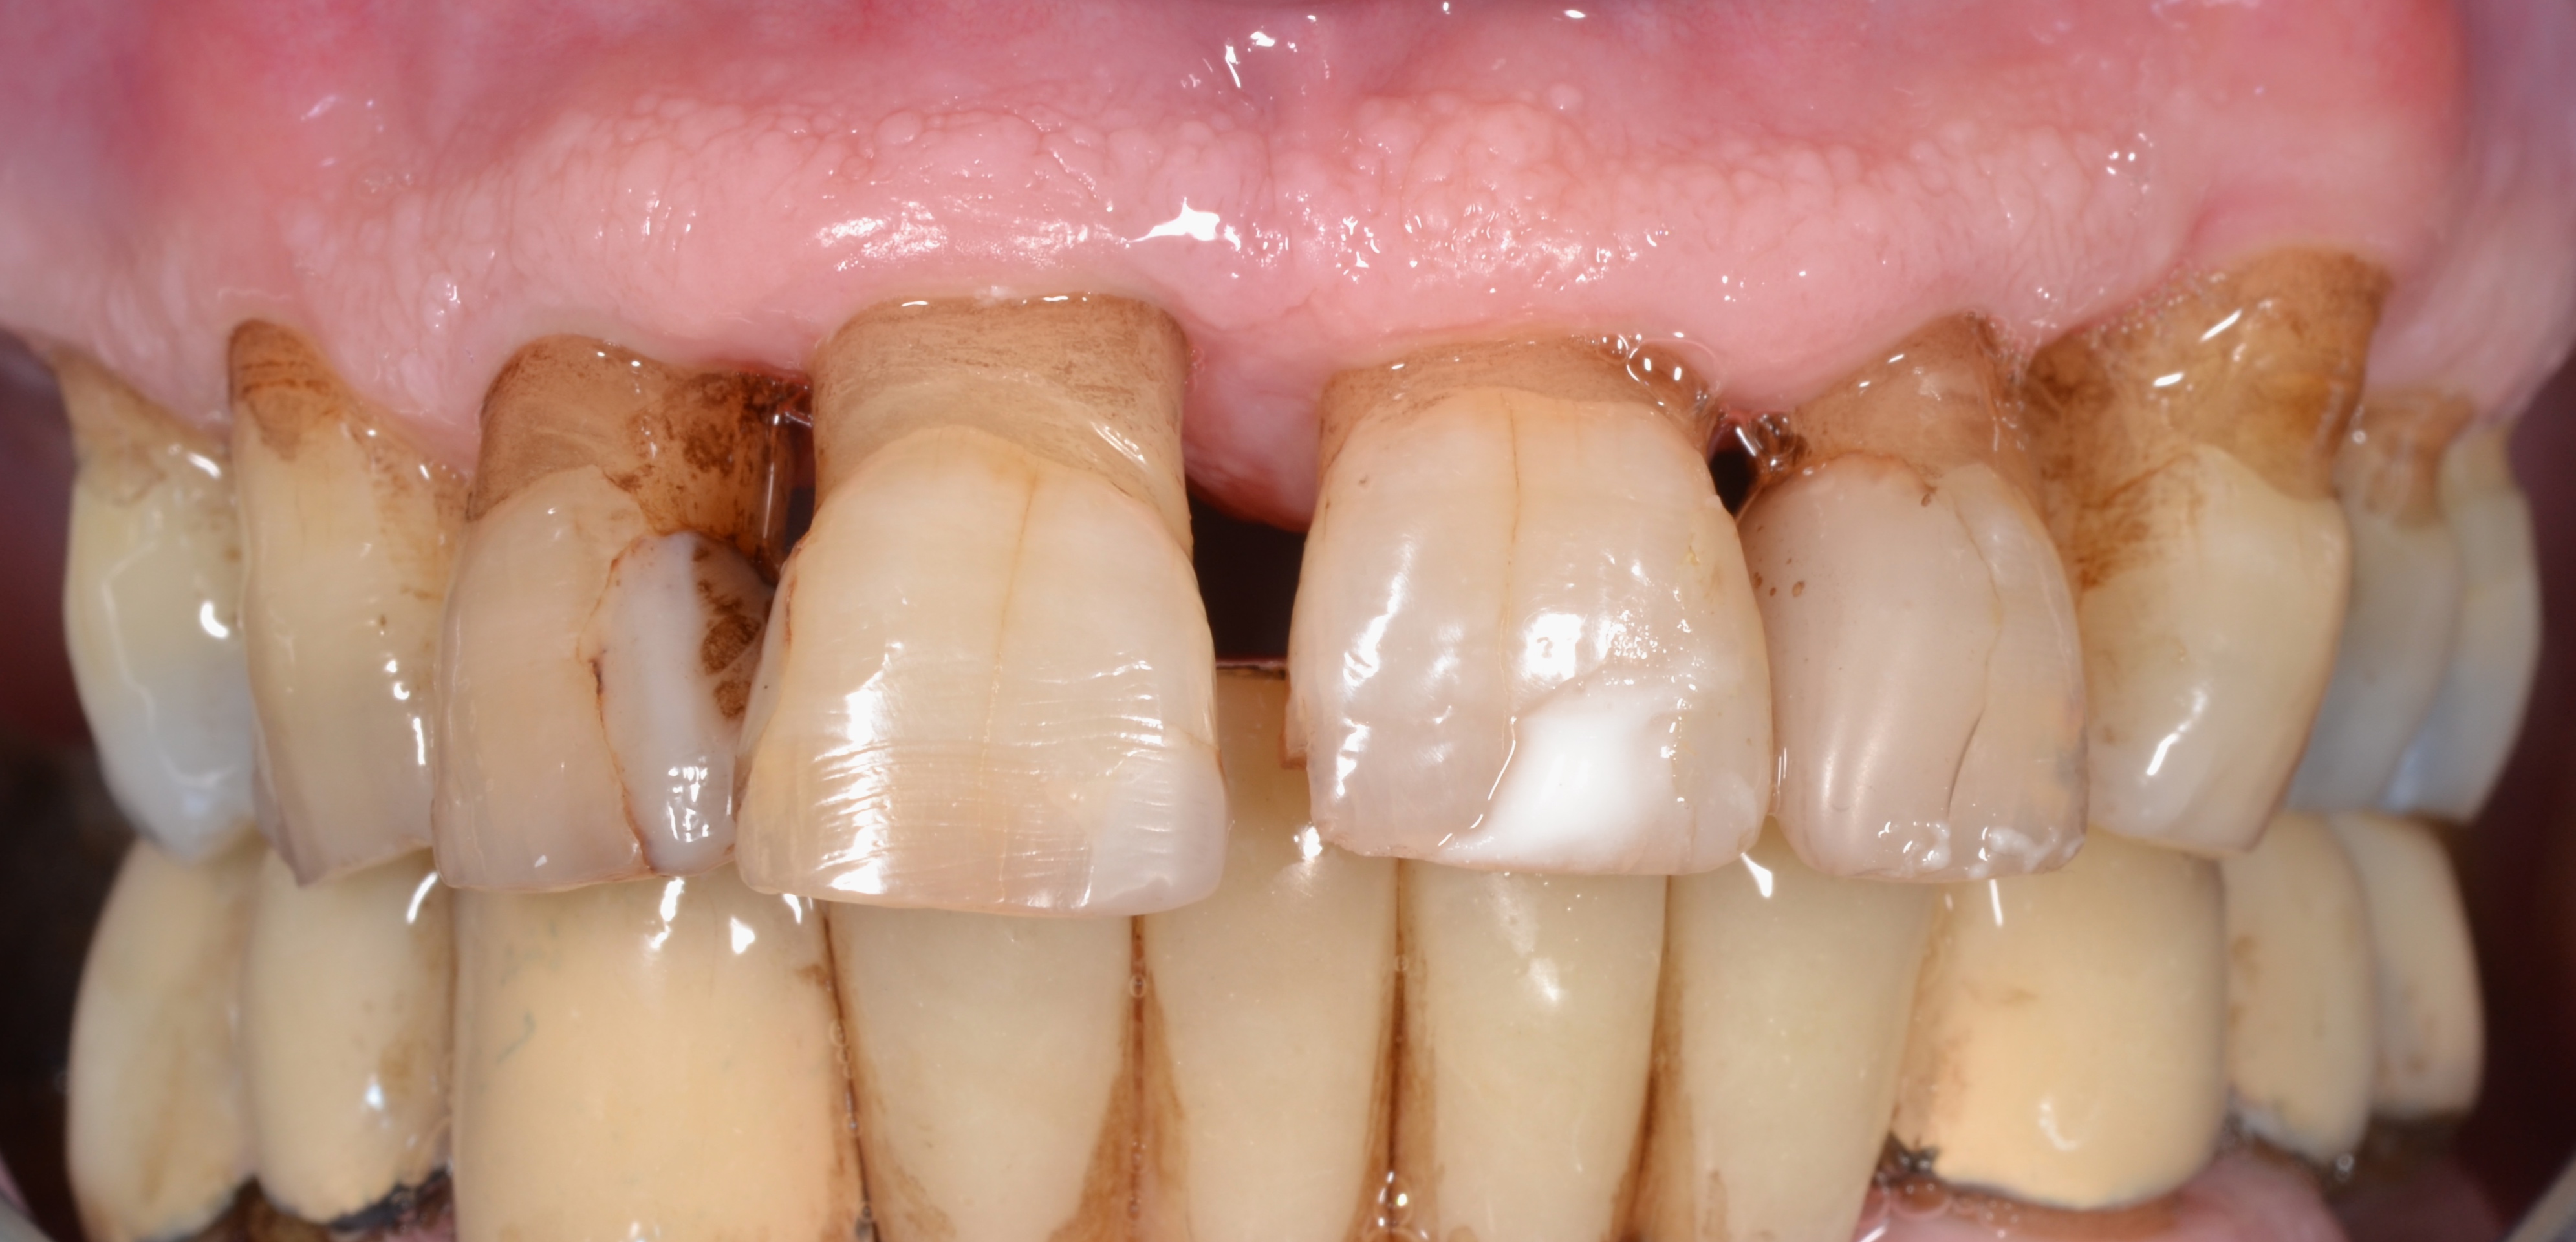

Před

Nejen kaz, ale i chronické onemocnění dásní (paradentóza) Vás může připravit o jeden nebo více zubů. Pana Vaška dlouhodobě trápila vysoká krvácivost dásní a vyšší viklavost zubů, zejména jedničky vpravo nahoře. Při vstupním vyšetření jsme zjistili paradentózní změny II. - III. stupně. Po instruktáži zubní hygieny následovala léčba paradentózy. Proběhl deep scaling (hloubkové odstranění zubního kamene z povrchu kořene zubů) horní i dolní čelisti společně s full mouth desinfection (celková desinfekce dutiny ústní pomocí antibiotik a výplachu úst).Veškerou léčbu měla na starosti hygienistka Petra Čekalová. Po léčbě paradentózy jsme museli vytrhnout jedničku vpravo nahoře pro výraznou ztrátu kosti. Po zhojení defektu zavedl Dr. Tomáš Křiva do vzniklého místa implantát. Za další tři měsíce jsme zhotovili s technikem Tomášem Forejtkem keramickou korunku. Protetickou fázi měl na starosti Dr. Filip Georges.